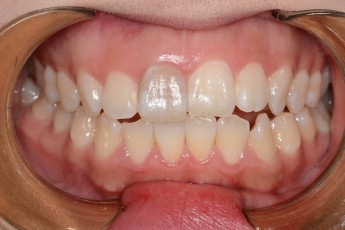

BEFORE & AFTER